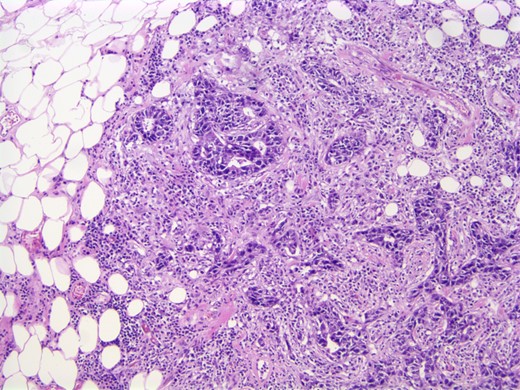

The findings were discussed with the patient and she subsequently underwent a modified radical mastectomy. Pathology of the specimens showed poorly differentiated apocrine carcinoma with extensive axillary node metastases (Fig. 4). The invasive carcinoma measured 1.5 × 1.4 × 1.3 cm without invasion into the skin or muscle. The margins were uninvolved.